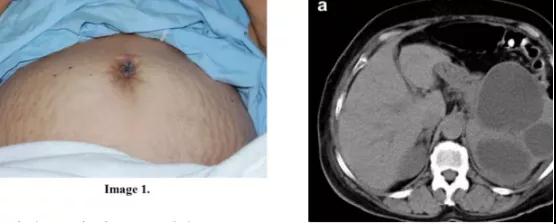

玛丽·约瑟夫结节的查体特征

玛丽·约瑟夫结节大小不一,绝大多数(70.6%)超过 2 cm 但通常小于 5 cm,呈白色、蓝紫色或棕红色,呈结节状,边界不清,质地韧(最常见)或坚硬,无痛或有压痛,表面皮肤可出现裂隙、溃疡或炎性表现,可伴血性、粘液性、浆液性或脓性分泌物。